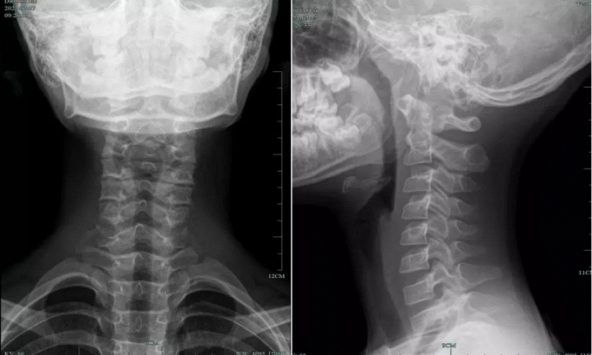

10 tuổi cột sống cổ đã cong vẹo, không cử động được vì thói quen của nhiều người